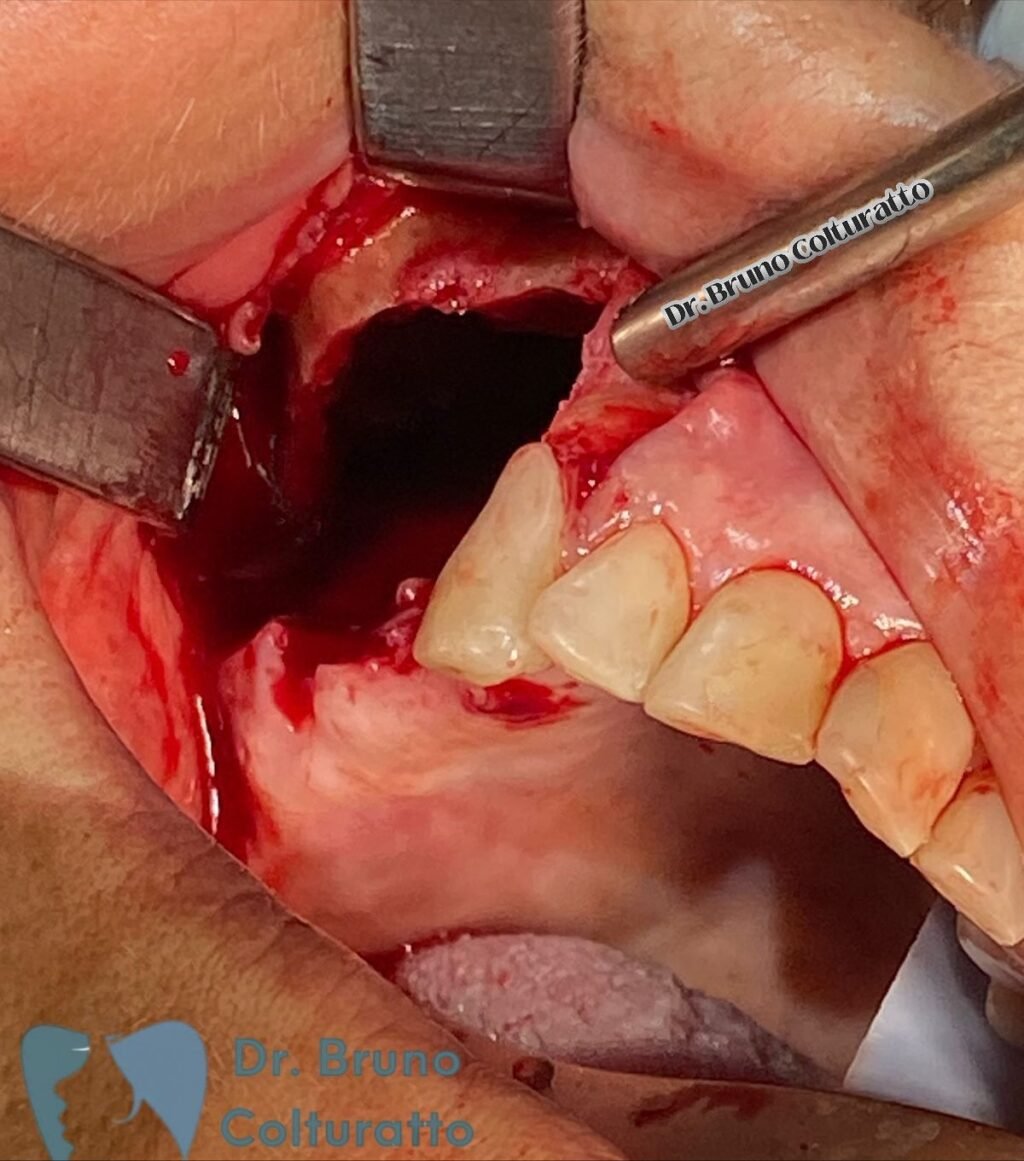

A Patologia Oral e Maxilofacial é a especialidade responsável pelo diagnóstico e tratamento de doenças que afetam a boca, mandíbula e estruturas faciais. Atua na identificação de lesões, cistos e tumores, garantindo diagnóstico preciso e tratamento adequado para preservar a saúde bucal e geral do paciente.